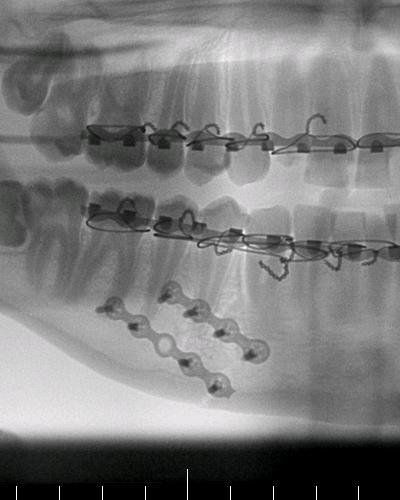

Trust me, this is just the beginning of quite a tale. I've been thru many highs and lows since this and I just want to take my time to write each piece effectively. It WILL be continued, and once again I would like to say it's 100% true, this is the story of my life over the last 8 years. I've wanted to tell my story, and have tried and tried to have the motivation to be able to endure and actually write it. Steemit is a new fire of motivation inside me, and now I feel it's time. I have nothing to gain from lying, and would like to build a good reputation as a writer here on Steemit. The image attached is my jaw, where the impact was, that part of the story yet to come.

I'm a dentist and it appears there is fracture in mandible and the doctors did a greatjob as they used an arch-bar for fixation of fracture

Yes in this picture, that's a definite fracture and after the archbars were removed the plates and screws remain. I'll try to be in as much detail about those parts as possible. Thanks for your interest, it's a good motivation to continue on.